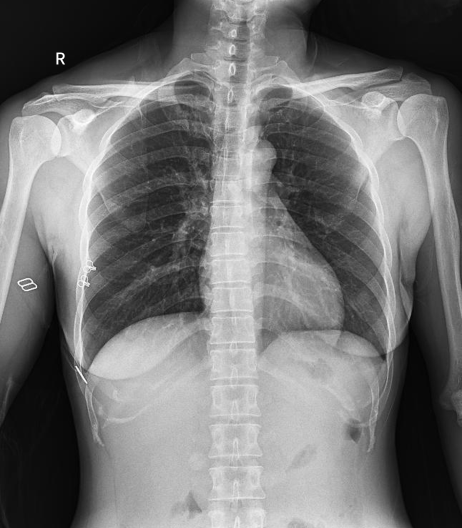

普利德醫(yī)療自主研發(fā)的新一代數(shù)字化X線透視攝影系統(tǒng),可應(yīng)用于DR攝影、數(shù)字透視、數(shù)字造影以及可視化精準DR拍片等多種臨床X線檢查領(lǐng)域。

● 17*17英寸的超高清像素動態(tài)平板探測器,更大的視野范圍,無需移動即可觀察整個動態(tài)過程,避免拖尾、噪聲對圖像的影響;

● 高效動態(tài)平板技術(shù),圖像不會有幾何畸變,提供高分辨率和精確的圖像,為醫(yī)生臨床診斷提供精準依據(jù);

● 最高幀速可達30幀/秒,動態(tài)采集清晰流暢,避免漏診、誤診情況的發(fā)生;

● 在可視過程或回放過程中,如發(fā)現(xiàn)疑似病灶,可進行毫秒級高清點片,隨時抓取單幀圖像,精準捕抓病灶。